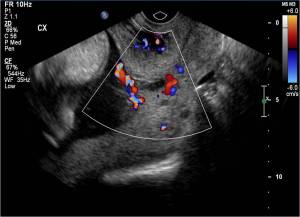

This is the ultrasound appearance of vasa previa. Vasa previa is when the umbilical cord vessels course across the internal cervical os, putting the patient and baby at risk for hemorrhage during delivery. Vasa previa is seen independently of placental and cord anomalies, as well as in cases of membranous cord insertion and succenturiate lobe placenta, where the placenta is split into two lobes and crossing fetal vessels are near the cervix.

If vasa previa goes undiagnosed, it results in 60-80% mortality. Fortunately this patient was diagnosed at 19 weeks, yielding a 97% survival rate.